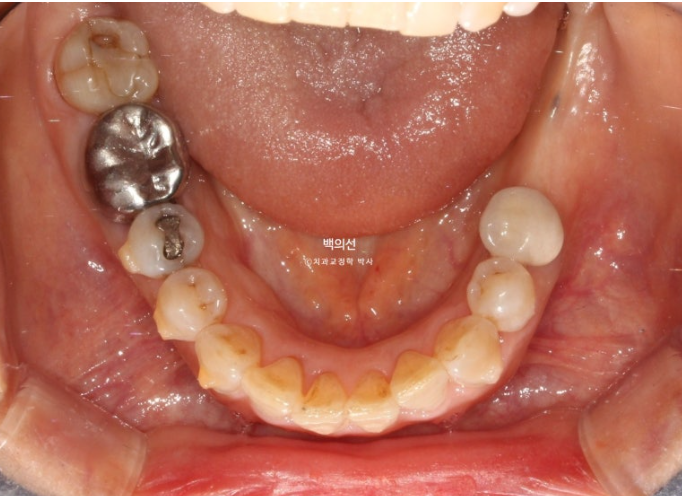

좌측 아래는 어금니가 빠진 지 오래된 상태입니다.

임플란트가 필요한 부분을 장기간 방치하면 대합치가 조금씩 솟아 내려오게 됩니다.

파란화살표 임플란트를 해넣기 위해서는 교정으로 내려온 대합치를 합입 시켜 올려야 합니다.

특히 내려온 큰어금니들 중 맨 뒤 제2대구치는 살릴 수 없어 타병원에서 발치진단이 나온 상태입니다.

잇몸이 뿌리끝까지 내려가 상태가 좋지 않습니다.

이 경우 치아를 미리 빼기 보다는, 불편함이 없다면 전략적으로 교정치료에 힘을 보태는데 이용하다가 교정치료가 끝나면 발치합니다.

아래 앞니는 치아가 많이 겹쳐져 있습니다.

특히 가운데 앞니와 옆 앞니는 50% 정도가 겹쳐진 상태

치아가 많이 겹쳐진 부위는 가지런히 배열이 끝나면 블랙트라이앵글이 크게 생깁니다.